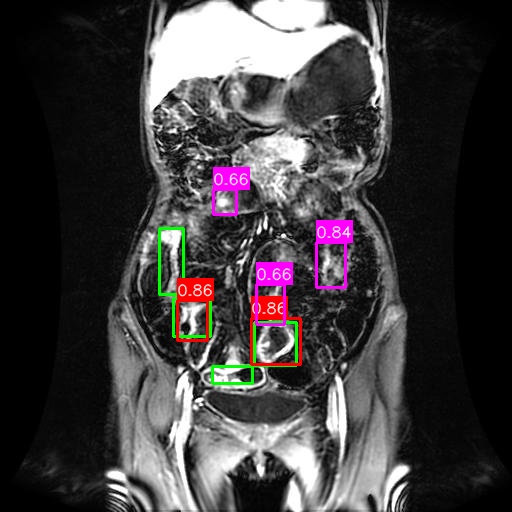

(a) Mask R-CNN [He2017MaskRCNN]

(b) DiffusionDet [Chen2023DiffusionDet_ICCV]

(c) DeFloMat (Ours)

Figure 3: Qualitative Comparison on Crohn’s Disease MRE Test Set. The figure compares detection results from (a) Mask R-CNN, (b) DiffusionDet (S=3S=3), and (c) DeFloMat (Ours, S=3S=3) on challenging MRE slices. Green boxes indicate True Positives (TP, IoU 0.1\geq 0.1), Red boxes indicate False Positives (FP), and Purple boxes indicate False Negatives (FN). DeFloMat consistently demonstrates superior localization quality and sensitivity: it successfully detects subtle inflammation regions (TP) that are often missed (FN, Purple boxes) by the Mask R-CNN baseline (Row 2, 4). Furthermore, DeFloMat provides tighter bounding box localization compared to DiffusionDet, confirming the benefit of learning the direct, deterministic flow field. The results show DeFloMat’s robustness in capturing varying sizes and numbers of inflammatory lesions.

Qualitative Assessment.

Figure 3 provides visual evidence of the models’ performance on challenging MRE slices, where inflammatory lesions can be subtle or obscured. The qualitative results underscore DeFloMat’s enhanced localization fidelity. In challenging cases (e.g., Row 2 and 4), Mask R-CNN and DiffusionDet frequently produce False Negatives (FN, Purple boxes), failing to detect clear inflammation sites. In contrast, DeFloMat reliably converts these FNs into True Positives (TP, Green boxes) by providing tighter and more accurate bounding box predictions. This suggests that the deterministic velocity field learned via Flow Matching is highly effective at precisely directing the proposal centers towards the true lesion locations, a characteristic that is vital for accurate clinical reporting. DeFloMat’s ability to achieve such precise localization with only S=3S=3 steps highlights its clinical utility for rapid diagnostic auxiliary systems.